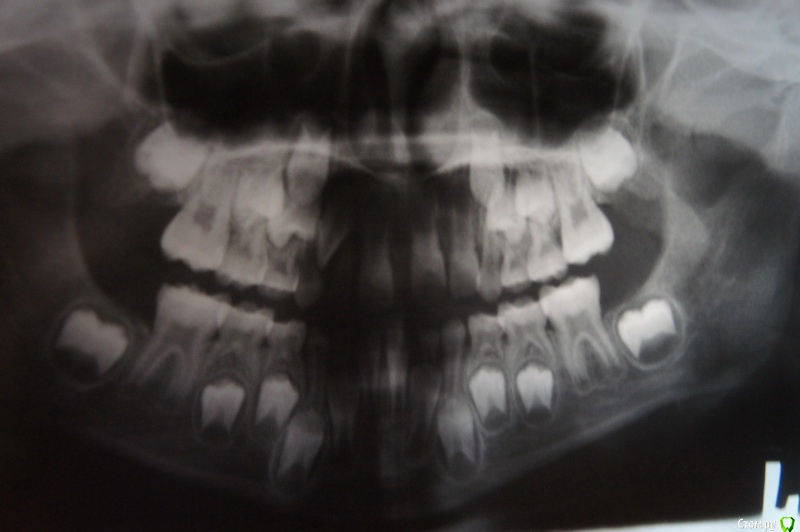

darida Опубликовано 2 февраля, 2016 Поделиться Опубликовано 2 февраля, 2016 (изменено) Ребёнок 8 лет (девочка). С рождения была массивная уздечка верхней губы (и "хвостик" из тканей десны между верхними передними резцами). Уздечку подрезали и подшили когда прорезались две постоянные единицы. Хвостик хирург не трогал, мотивируя тем, что когда зубы начнут сдвигаться (с помощью пластинки или брекетов - как решит ортодонт) - он рассосётся, так как мягкие ткани более податлитвы, чем рубцовые, которые образуется в случае его подрезания. Это было год назад.Через месяц после подрезания пошли к ортодонту. Ортодонт сказала приходить через год когда вылезут полностью постоянные двойки верхние, чтобы была возможность зацепить за них пластинку для устранения передней щели. На тот момент была только левая постоянная двойка, но кривая. Правая двойка по снимку тоже видно было, что вылезет кривой. Молочную правую двойку удалили вместе с подрезанием уздечки, так как не было даже намёка на шатание, а постоянная уже почти проклюнулась через десну над молочной.Двойки ортодонт сказала, что ровнять не будем пока не сменятся клыки.Несколько месяцев назад выпал сам правый молочный клык. Скорее всего его вытолкала эта постоянная двойка, так как очень-очень плотно стояла к нему, не было ни малейшей щели между ними (а вот между единицей и двойкой правыми - наоборот огромная щель, и многие (не врачи, естественно) даже принимают двойку за клык).В настоящее время побыли у другого ортодонта, которая предложила такой вариант: ориентировочно раз в год делать снимок, и когда будет видно, что постоянный клык уже продвигается вниз и скоро вылезет - поставить на передние верхние четыре зуба частичную брекет-систему (я уточняла на счет крепления - за шестёрки или как, но она сказала, что только именно на четыре зуба и всё) на месяца четыре ориентировочно, так как однокоренные зубы быстро сдвигаются и много времени не потребуется. А потом после становления резцов на место - установить со стороны языка "проволоку" до момента прорезывания клыков, чтобы зубы назад не разъехались.Пластинку она ставить категорически против, так как она наклоняет только коронку зуба и практически не воздействует на корень, то есть не подвигает зубы, а только наклоняет, а нам нужно именно передвигать (сдвигать) их.Прокомментируйте, пожалуйста, ситуацию и дайте советы и рекомендации.Если этих фото недостаточно, скажите какие ещё добавить.Снимок годичной давности, когда ещё был в наличии молочный правый клык. Изменено 2 февраля, 2016 пользователем darida Ссылка на комментарий